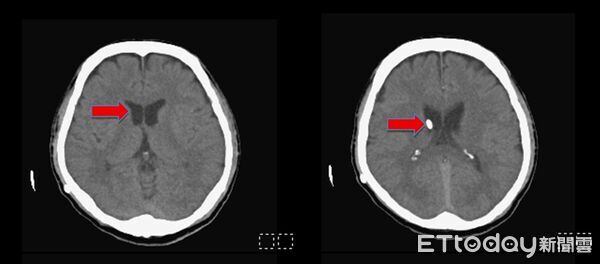

▲術後半年,所有脹大的腦室皆已恢復正常大小,可見到所放置右側腦室的導管(紅色箭頭)。(圖/記者許宥孺翻攝)

陳志豪醫師強調,早期辨識與介入治療是改善預後的關鍵,臨床可透過電腦斷層(CT)或磁振造影(MRI)影像學判斷及病程追蹤來評估是否需進行分流手術。從臨床經驗及研究都顯示,適時進行腦脊髓液分流手術可顯著提升病人的神經功能與生活品質。個案經過手術後才恢復清楚意識及記憶,自述「彷彿獲得重生」,術後半年追蹤,原先腫大的腦室已恢復正常大小,也已重返工作崗位。